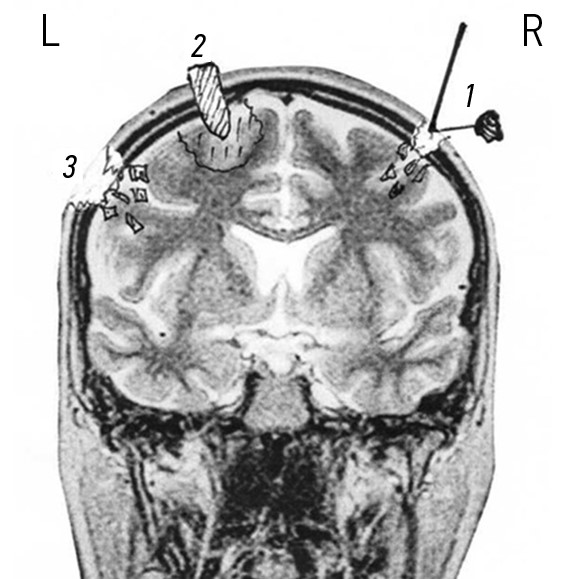

На рис. 2 представлены зоны поражения сосудов ГМ при огнестрельных проникающих черепно-мозговых ранениях.

Рис. 2. Магнитно-резонансная ангиография головного мозга с зонами расположения сосудов: 1 — сосуды подкорковых образований, желудочков и ствола головного мозга; 2 — сосуды коры головного мозга.